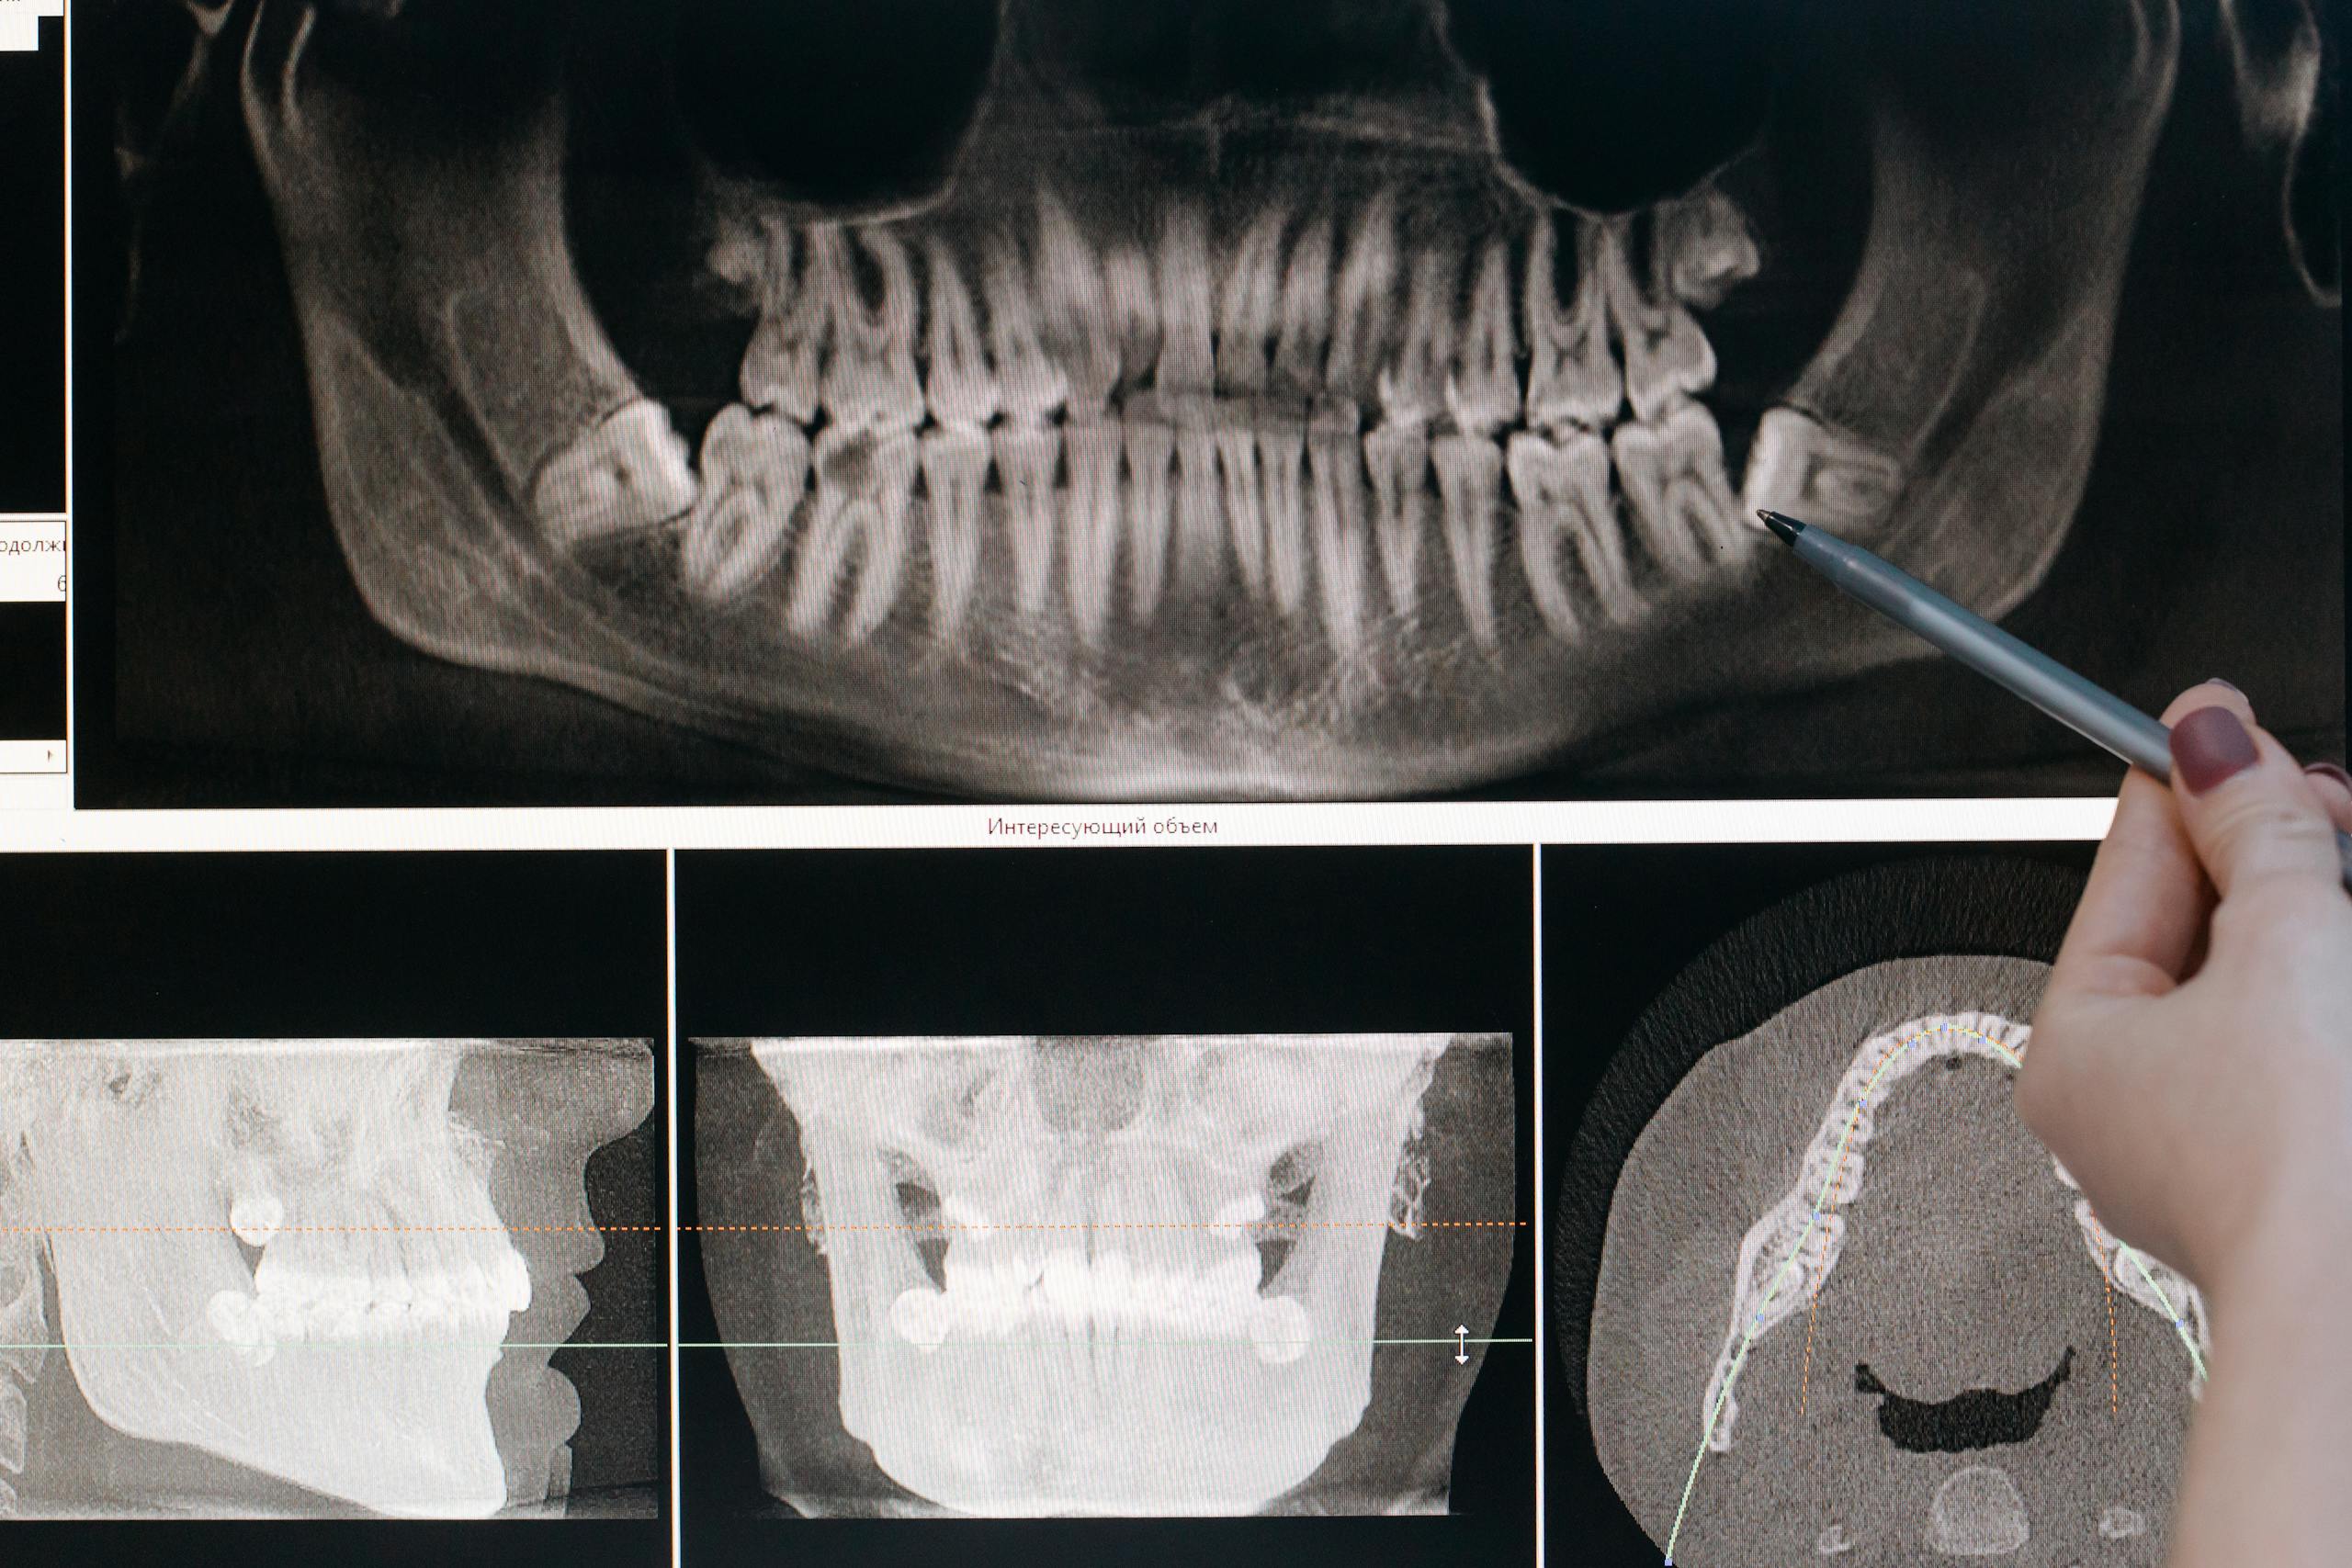

Неправильное расположение зуба или ретинированный зуб, сложная корневая система и ряд других аномалий может привести к появлению осложнений. Среди них воспаление, высокая температура, боли и другое. Лечение невозможно, рекомендованная мера – удаление.

Невозможность лечения каналов

В некоторых ситуациях провести лечение каналов невозможно даже с помощью микроскопа. Чтобы купировать развитие дальнейших осложнений, лучше удалить проблемный зуб. Цена на удаление зуба и быстрые сроки восстановления делают эту меру предпочтительной.

Симптомами травматического повреждения корня являются болевые ощущения при механическом воздействии на зуб, отечность и покраснение слизистых, в некоторых случаях – подвижность. В зависимости от тяжести ситуации может быть показано удаление поврежденного зуба.